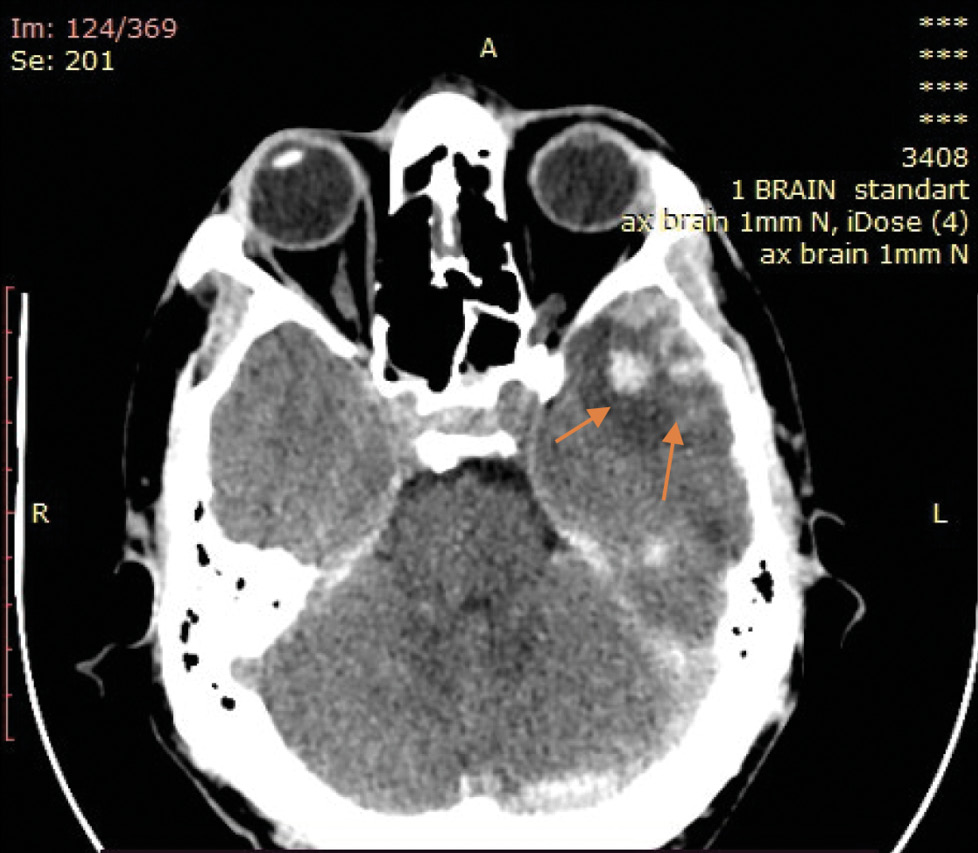

На экспертизу дополнительно представлены результаты мультиспиральной компьютерной томографии головного мозга гражданина Л., благодаря которым экспертом выявлено следующее. На серии компьютерных томограмм (с последующим 3D-моделированием) в лобно-височно-теменной области слева субдуральная гематома максимальной толщиной до 4 мм. В полюсно-базальных отделах левой височной доли определяются мелкие очаги геморрагической плотности, местами сливного характера (рис. 1, 2). Боковые желудочки симметричные. Срединные структуры мозга не смещены. Субарахноидальное пространство нивелировано слева. В бороздах мозга левой височной, левой теменной долей геморрагическое содержимое (субарахноидальное кровоизлияние), малая эпидуральная гематома правой теменно-височной области. Перелом сосцевидного отростка правой височной кости: линия перелома распространяется на пирамиду правой височной кости и заднюю стенку наружного слухового прохода (рис. 3–5). Наличие геморрагического содержимого в ячейках правого сосцевидного отростка, в антруме справа и в правой барабанной полости.

Рис. 1. Мультиспиральная компьютерная томография головного мозга: очаги ушиба головного мозга (стрелки) в полюсных отделах левой височной доли на аксиальном срезе.

Характерная локализация и морфологические особенности внутренних телесных повреждений, выявленных при мультиспиральной компьютерной томографии головного мозга, их взаиморасположение, а также вид и локализация наружных телесных повреждений вкупе с данными материалов дела позволили прийти к следующим выводам о механизме данной травмы: ушибленная рана верхней губы слева возникла в результате ударного воздействия твёрдого тупого предмета (удар кулаком) с последующим падением и ударом пострадавшего о твёрдый тупой предмет (правая от него стена коридора) правой височной и теменной областью справа, с формированием в зоне удара головой о стену локального перелома сосцевидного отростка правой височной кости с переходом на пирамиду височной кости и заднюю стенку наружного слухового прохода, эпидуральной гематомы правой теменно-височной области, а в зоне противоудара ― очагов ушибов полюсно-базальных отделов левой височной доли, субдуральной гематомы левой лобно-височно-теменной области с субарахноидальным кровоизлиянием левой височной, левой теменной долей.